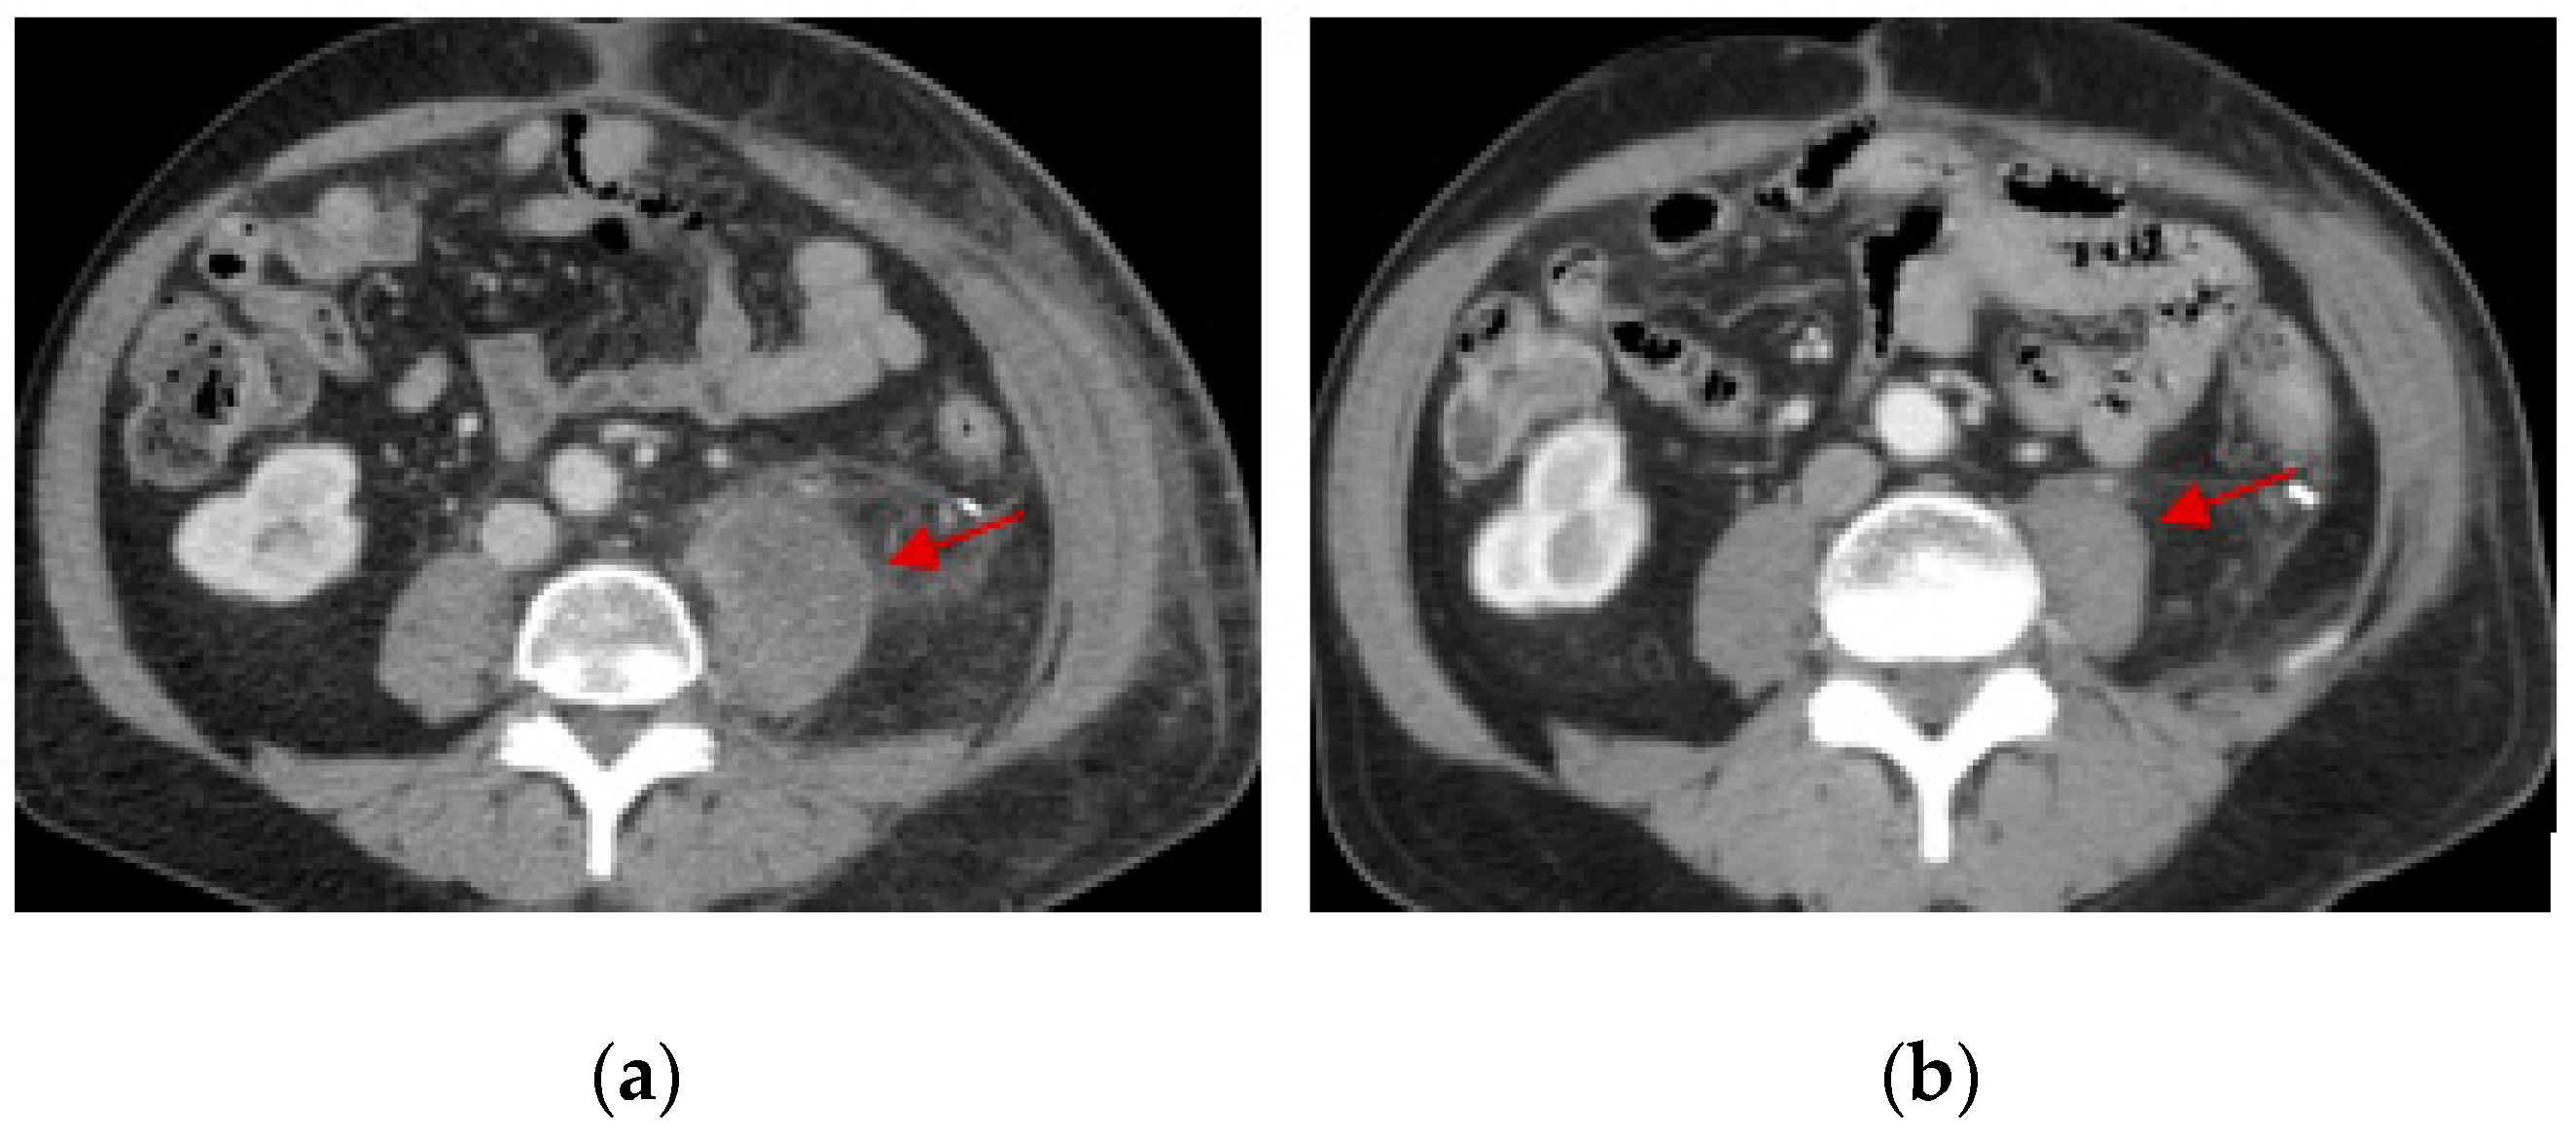

- Mori, Y.; Kinoshita, S.; Kanamori, T.; Kataoka, H.; Joh, T.; Iida, S.; Takemoto, M.; Kondo, M.; Kuroda, J.; Komatsu, H. The Successful Treatment of Metastatic Extraosseous Ewing Sarcoma with Pazopanib. Intern. Med. 2018, 57, 2753–2757. [Google Scholar] [CrossRef]